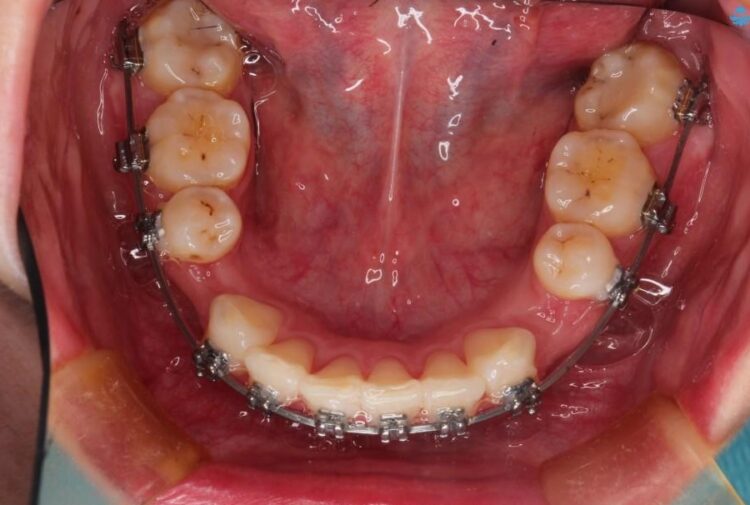

治療費の安い矯正治療を希望されていたため、メタルのワイヤー装置にて治療する計画にしました。また、歯みがきが苦手だったため、矯正治療をする前に徹底的にブラッシング指導を行いました。

出ている歯を引っ込めるためのスペースを作るため、上下左右の小臼歯を抜歯し、ワイヤー矯正を行いました。治療後は、口元がスッキリとしたことで患者様にも喜んでいいただきました。